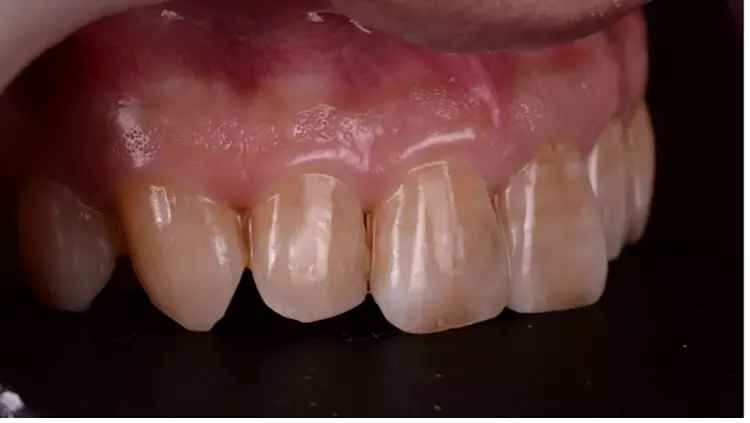

Der 56-jährige Patient stellte sich mit einer dezementierten Krone an Zahn 22 und insuffizientem Zahnersatz an Zahn 21 vor. Die koronale Leakage bestand schon mehrere Tage, bevor der Patient die Praxis aufsuchte. Die Ausgangssituation zeigte, dass beide Zähne zuvor wurzelkanalbehandelt waren (Abb. 1). Nach eingehender Röntgendiagnostik wurde entschieden, die defekte Krone an Zahn 21 zu entfernen und zunächst ein adäquates Kariesmanagement zu betreiben (Abb. 2).